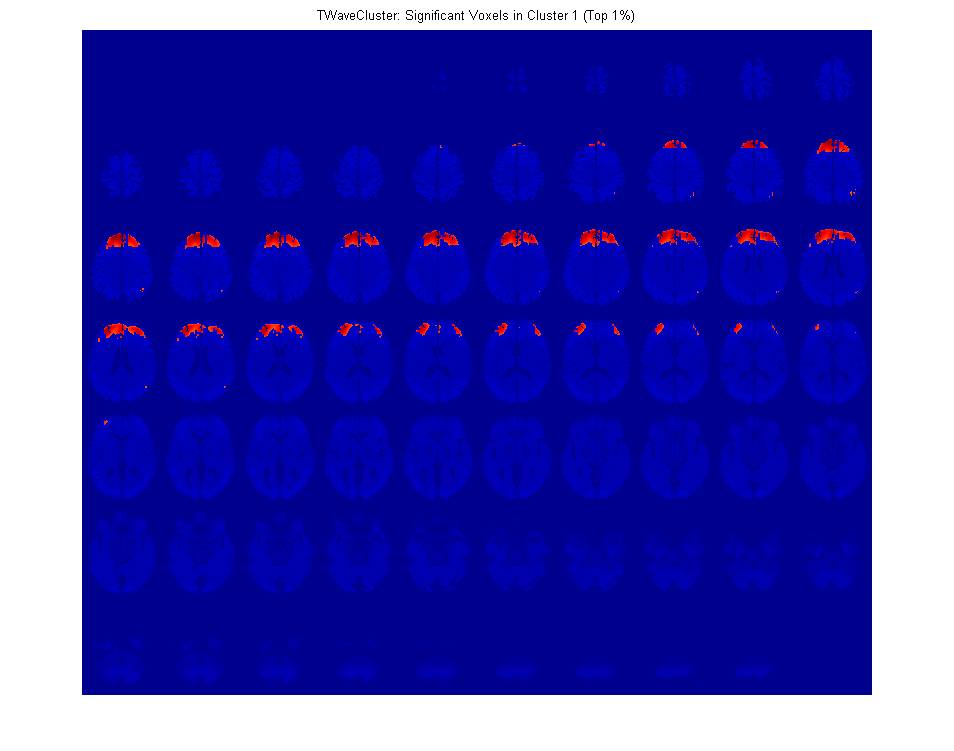

My dissertation work is based primarily on higher-order analogues of singular value decomposition (high-order SVD, PARAFAC, and Tucker) coupled with a variety of wavelet-based techniques and involved creation of a comprehensive data mining framework for classification, co-clustering, concept discovery (e.g. detecting handedness in subjects based on fMRI scans), summarization, and compression of high-order spatiotemporal datasets, with principal applications in fMRI. In the course of this work I also devised a tensor-theoretic multidimensional discrete wavelet transform, extended the WaveCluster algorithm to accept real-valued high-order image data, created a novel clustering algorithm based on WaveCluster called TWaveCluster, mitigated the massive partial volume effect inherent in grid-based segmentation (by deforming the grid in a context-sensitive manner prior to clustering), released the first public implementation of WaveCluster (which I have opensourced under the GPLv3), and discovered quite a few interesting new results about motor and cognitive task activation patterns in the human brain.

For instance, I discovered that performing difficult cognitive tasks lights up the same areas of the brain that process physical pain, added evidence supporting a hypothesis that ipsilateral activation is important in motor task based learning (most activation is contralateral), and localized the spatiotemporal patterns of activation found in working memory tasks.